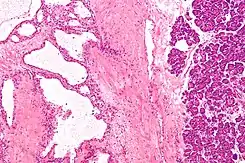

Micrografía mostrando un cistoadenoma seroso del páncreas. H&E stain.

En contraste con algunos de los otros tumores del páncreas que forman quistes (como la neoplasia mucinosa papilar intraductal y la neoplasia quística mucinosa), las neoplasias quísticas serosas son casi siempre completamente benignas. Hay algunas excepciones; en raras ocasiones, se han descrito casos de cistoadenocarcinomas serosos malignos aislados.[3] Además, las neoplasias quísticas serosas crecen lentamente y, si crecen lo suficiente, pueden presionar los órganos adyacentes y causar síntomas.

Los patólogos clasifican las neoplasias quísticas serosas en dos grandes grupos. Aquellas que son benignas, que no se han diseminado a otros órganos, se denominan "cistoadenomas serosos".[4] Los cistoadenomas serosos pueden subdividirse en microquístico, oligocístico (o macrocístico), sólido, neoplasia endocrina mixta y neoplasia serosa asociada a VHL. Este último esquema de clasificación es útil porque destaca la variedad de aspectos y las asociaciones clínicas de estas neoplasias. Las neoplasias quísticas serosas que se han diseminado ("metastatizado") a otro órgano se consideran malignas y se denominan "cistoadenocarcinoma seroso".